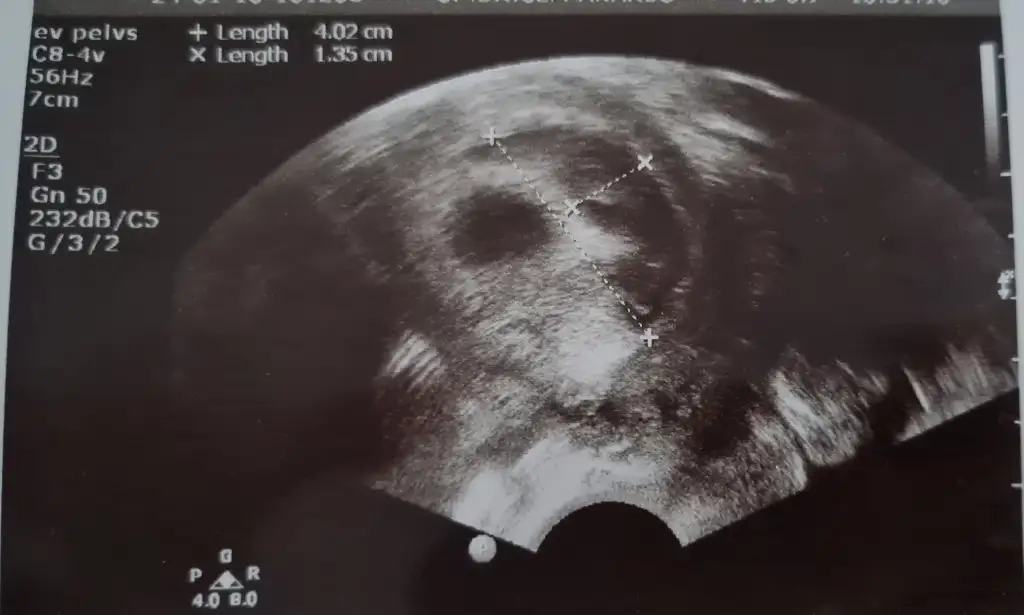

arkadaslar bebegimi ilk gormeye gittigimizde 5+4 tu yolk kesesini gorduk ve gayet iyiydi hersey smdi 7+2 de hem bebisimi hemde kalp atisini gormeye gitcektik 7+1 birgun once gece ani bi kanamayla acile gittik kanamam adet gibi yogundu ve asiri buyuk ciger gibi kan pihtilari dustu ertesi gun doktorumla randovumuz vardi zaten gittik bebisin kalp atisini duyduk bebekte iyiydi kesede zarar gormemisti ama kanama alanima acildeki doktorda kendi doktorumda cok buyuk dedi 4.2 cmye 1.35 cm cikti benim bebegim tup bebek gunde 3 kere yumurta toplamadan beri fitil seklinde progestan 200 kullaniyodum smdi + olarak progestan dex igne verdi gunde 1 adet doktorumun dedigi dinlenmem agir is yapmamam bebek eger saglikliyla bisey olmicagini soyledi hatta kanin akmasi hastalari korkutsada onu memnun ediyomus basinc olusturmuyomus boylelikle icerde bebek buyudukce rahimde daha fazla yer kaplamaya basladikca kanama dururmus bu boyutlarda bi kanama yasayan var mi yada boyle bi kanama yasayip sonrasi ne oldu kanama alaninin gorselini ekliyorum tarali alan

benim dun kontrolum vardi kanama alanimiz daha cok buyumus alanimiz onceden 4 x 1.3 cm di simdi 5 x 4 kusur dedi ama bebis gayet iyi benim doktorum kanin akmasini istiyoki birikmesin iceride basinc yapmasin diye birde akarsa daha hizli bosalir vucudun emmesini beklersek daha gec biter diyo o yuzden bence sizde korkmayin sizin cmleriniz nasil ben eski ve gunceli koyuyim tekrar ama bu kontrolde karindan baktigi icin sol saga dondu aynalama oldu yani siz tukenmezle cizili olan resmi kan alani sagda dusunun lutfen